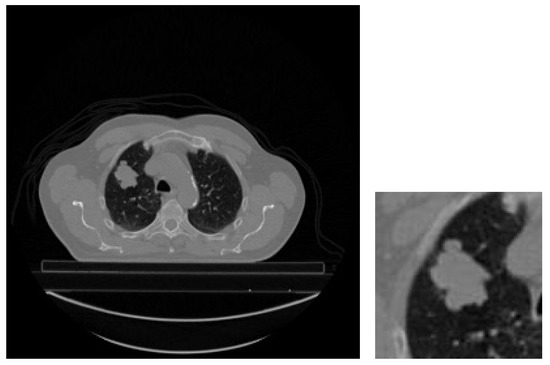

While performing the tests, the censored observations are discarded, and the input images of the remaining patients are converted to gray level, 240 × 240 in size, and 5-slice (240 × 240 × 5). When adjusting the 5-slice images, the slice with the largest tumor area among the slices containing the tumor areas is selected. In order to perform this process, first, the contours of the tumor regions are determined in the CT slices of each patient containing GTV-1. Using the extreme points of the tumor perimeter, the area is found by drawing the minimum rectangle surrounding the tumor area. To preserve spatial information, the largest tumor slice has two adjacent slices before and two after that contain the tumor. If the number of slices containing the tumor region is greater than or equal to 5, it and four neighboring slices are kept. If the number of slices containing tumor regions is less than 5, they are oversampled (copied) and saved until the number of slices containing tumors is five. Finally, all input images are normalized between 0–1 to ensure that the neural network gives more successful results. Figure 7 shows an example input image sent to the model.

Figure 7. An example input image for the model.